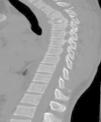

Se solicitaron radiografías de hombro y escápula bilaterales, en las cuales se observaron fracturas del cuerpo de la escápula izquierda con conminución, leve desplazamiento y angulación, además de fractura del cuerpo de la escápula derecha con desplazamiento sin angulación significativa (figs. 1–2). Por sospecha de contusión pulmonar se solicitó angiografía por tomografía Computada (angio-TC), la cual descartó alteraciones a nivel pulmonar, pero puso de manifiesto fracturas de los cuerpos vertebrales de T3 y T4 por acuñamiento con invasión del canal medular en T4, fracturas de las apófisis espinosas de T2 y T3, y fractura transversal no deprimida del cuerpo del esternón (figs. 3–5).

Las fracturas de escápula se trataron de manera conservadora; requirió intervención del traumatismo de la columna torácica mediante la realización de corpectomía de T4 con la aplicación de un cilindro intercorporal y fijación transpedicular con instrumentación posterior por el Servicio de Neurocirugía (fig. 6). El paciente evolucionó adecuadamente sin presentar síntomas neurológicos ni otros hallazgos que impidieran darle el alta hospitalaria.